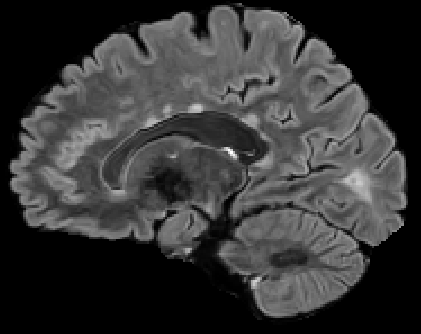

Recently, segmentation methods based on Convolutional Neural Networks (CNNs) showed promising performance in automatic Multiple Sclerosis (MS) lesions segmentation. These techniques have even outperformed human experts in controlled evaluation conditions such as Longitudinal MS Lesion Segmentation Challenge (ISBI Challenge). However state-of-the-art approaches trained to perform well on highly-controlled datasets fail to generalize on clinical data from unseen datasets. Instead of proposing another improvement of the segmentation accuracy, we propose a novel method robust to domain shift and performing well on unseen datasets, called DeepLesionBrain (DLB). This generalization property results from three main contributions. First, DLB is based on a large group of compact 3D CNNs. This spatially distributed strategy ensures a robust prediction despite the risk of generalization failure of some individual networks. Second, DLB includes a new image quality data augmentation to reduce dependency to training data specificity (e.g., acquisition protocol). Finally, to learn a more generalizable representation of MS lesions, we propose a hierarchical specialization learning (HSL). HSL is performed by pre-training a generic network over the whole brain, before using its weights as initialization to locally specialized networks. By this end, DLB learns both generic features extracted at global image level and specific features extracted at local image level. DLB generalization was validated in cross-dataset experiments on MSSEG'16, ISBI challenge, and in-house datasets. During experiments, DLB showed higher segmentation accuracy, better segmentation consistency and greater generalization performance compared to state-of-the-art methods. Therefore, DLB offers a robust framework well-suited for clinical practice.